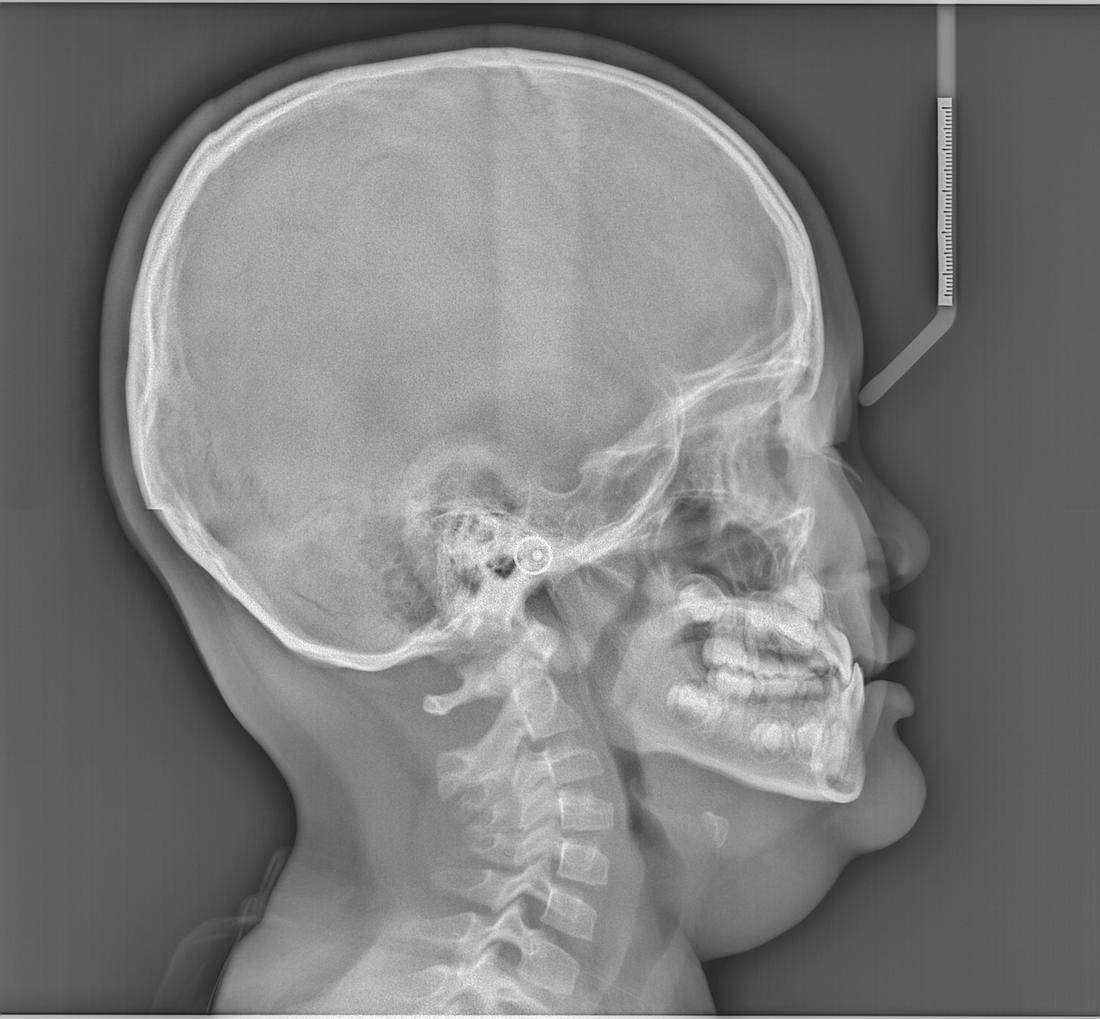

演示图片1

精确识别头颅侧位片中17个关键解剖标志点